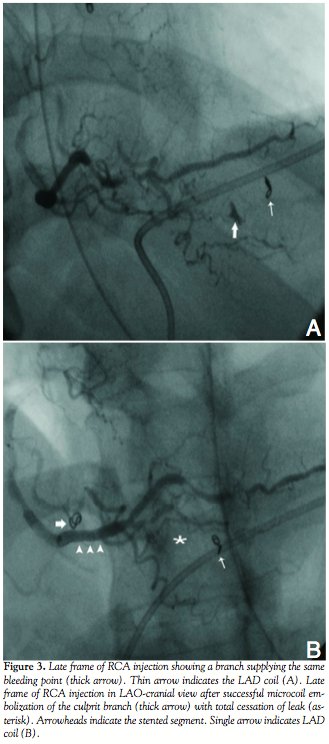

into the same branch during LAD angioplasty. Prolonged balloon inflation at the origin of the culprit vessel did not yield satisfactory result. Therefore, we decided to perform microcoil embolization of the distal LAD. A MiraFlex microcatheter (Cook) with inner diameter of .021-inch was positioned near the origin of the feeding vessel and embolization was performed using an 18-2-2 MCWE HILAL microcoil (Cook). The result was total occlusion of the distal LAD including the culprit branch (Figure 2B). The patient experienced angina of moderate severity, which subsided gradually. About 6 H later, he developed hypotension and echocardiogram revealed re-accumulation of pericardial fluid with evidence of cardiac tamponade. The patient was shifted to the catheterization laboratory, and left coronary angiogram confirmed total occlusion of the distal LAD, and no evidence of reopening of the coronary leak. Pericardiocentesis was continued, which showed aspiration of fresh blood, indicating ongoing bleeding into the pericardial cavity. Therefore, RCA injection was also performed to rule out any leak from the right side. To our surprise, a marginal branch of the RCA was seen supplying the same culprit vessel on left through collateral causing continuous loss of blood (Figure 3A). Selective microcoil embolization of the marginal branch using 18-2-2 MCWE HILAL microcoil (Cook) could successfully close it, resulting in total cessation of blood loss (Figure 3B). Recovery of the patient was mostly uneventful except for transient elevation of serum creatinine level.